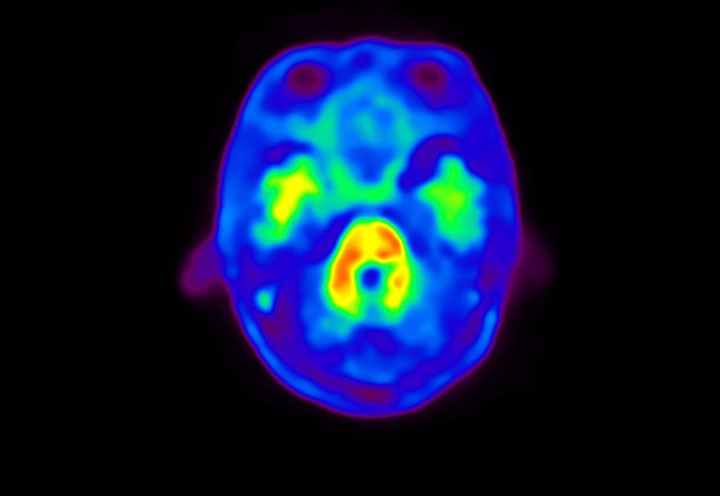

Head / Case4 : Amyloid

Courtesy : Kindai University Hospital

- Imaging protocol

- Injected dose: 3.21 MBq/kg, 18F-Flutemetamol

- Uptake time: 100 minutes

- Scan time: 20 minutes